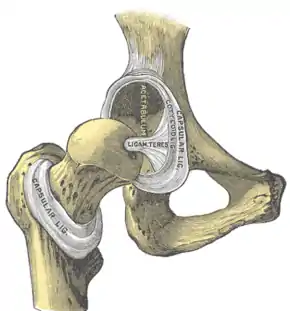

Intracapsular ligament. Left hip joint from within pelvis with the acetabular floor removed (left); right hip joint with capsule removed, anterior aspect (right).

The hip joint is reinforced by four ligaments, of which three are extracapsular and one intracapsular.

The extracapsular ligaments are the iliofemoral, ischiofemoral, and pubofemoral ligaments attached to the bones of the pelvis (the ilium, ischium, and pubis respectively). All three strengthen the capsule and prevent an excessive range of movement in the joint. Of these, the Y-shaped and twisted iliofemoral ligament is the strongest ligament in the human body. It has a tensile strength of 350 kg.[22] Iliofemoral ligament is a thickening of the anterior capsule extending from anterior inferior iliac spine to intertrochanteric line.[5] Ischiofemoral ligament is the thickening of posterior capsule of the hip and pubofemoral ligament is the thickening of the inferior capsule.[5] In the upright position, iliofemoral ligament prevents the trunk from falling backward without the need for muscular activity, thus preventing excessive hyperextension. In the sitting position, it becomes relaxed, thus permitting the pelvis to tilt backward into its sitting position. Ischiofemoral prevents excessive extension and the pubofemoral ligament prevents excess abduction and extension.[24]

The zona orbicularis, which lies like a collar around the most narrow part of the femoral neck, is covered by the other ligaments which partly radiate into it. The zona orbicularis acts like a buttonhole on the femoral head and assists in maintaining the contact in the joint.[22] All three ligaments become taut when the joint is extended - this stabilises the joint, and reduces the energy demand of muscles when standing.[25]

The intracapsular ligament, the ligamentum teres, is attached to a depression in the acetabulum (the acetabular notch) and a depression on the femoral head (the fovea of the head). It is only stretched when the hip is dislocated, and may then prevent further displacement.[22] It is not that important as a ligament but can often be vitally important as a conduit of a small artery to the head of the femur, that is, the foveal artery.[26] This artery is not present in everyone but can become the only blood supply to the bone in the head of the femur when the neck of the femur is fractured or disrupted by injury in childhood.[27]